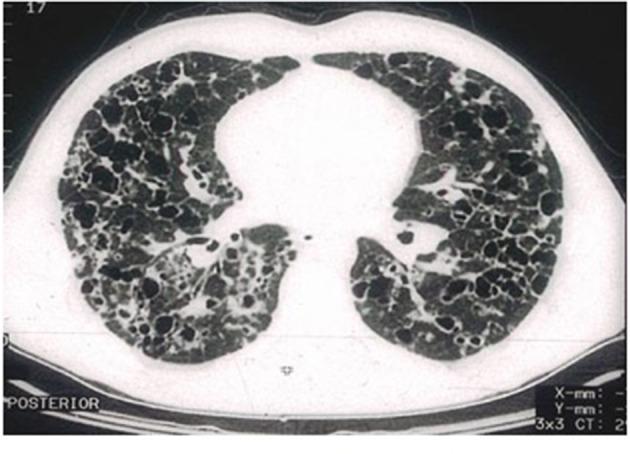

Pulmonary Langerhans cell (LC) histiocytosis (PLCH) has unknown cause and is a rare neoplastic disorder characterized by the infiltration of lungs and various organs by bone marrow-derived Langerhans cells with an accompanying strong inflammatory response. These cells carry somatic mutations of gene and/or , and genes, which cause activation of the mitogen-activated protein kinase (MAPK)/extracellular signal-regulated kinase (ERK) signaling pathway. PLCH occurs predominantly in young smokers, without gender predominance. Lungs might be involved as an isolated organ or as part of a multiorgan disease. High-resolution computed chest tomography plays an outstanding role in PLCH diagnosis. The typical radiological picture of PLCH is the presence of small intralobular nodules, "tree in bud" opacities, cavitated nodules, and thin- and thick-walled cysts, frequently confluent. Histological examination of the lesion and demonstration of characteristic eosinophilic granulomas with the presence of LCs that display antigen CD1a or CD207 in immunohistochemistry are required for definite diagnosis. Smoking cessation is the most important recommendation for PLCH patients, but treatment of progressive PLCH and multisystem disease is based on chemotherapy. Recently, new targeted therapies have been implemented.

肺朗格汉斯细胞(LC)组织细胞增多症(PLCH)病因不明,是一种罕见的肿瘤性疾病,其特征是骨髓来源的朗格汉斯细胞浸润肺和各种器官,并伴有强烈的炎症反应。这些细胞携带基因和/或基因以及基因的体细胞突变,导致丝裂原活化蛋白激酶(MAPK)/细胞外信号调节激酶(ERK)信号通路激活。PLCH主要发生在年轻吸烟者中,无性别差异。肺部可能作为孤立器官受累,也可能是多器官疾病的一部分。高分辨率胸部计算机断层扫描在PLCH诊断中起着重要作用。PLCH典型的放射学表现为小叶内小结节、“树芽”状阴影、空洞性结节以及薄壁和厚壁囊肿,常相互融合。明确诊断需要对病变进行组织学检查,并在免疫组织化学中显示具有表达抗原CD1a或CD207的LC的特征性嗜酸性肉芽肿。对PLCH患者最重要的建议是戒烟,但对于进行性PLCH和多系统疾病的治疗基于化疗。最近,已实施了新的靶向治疗。